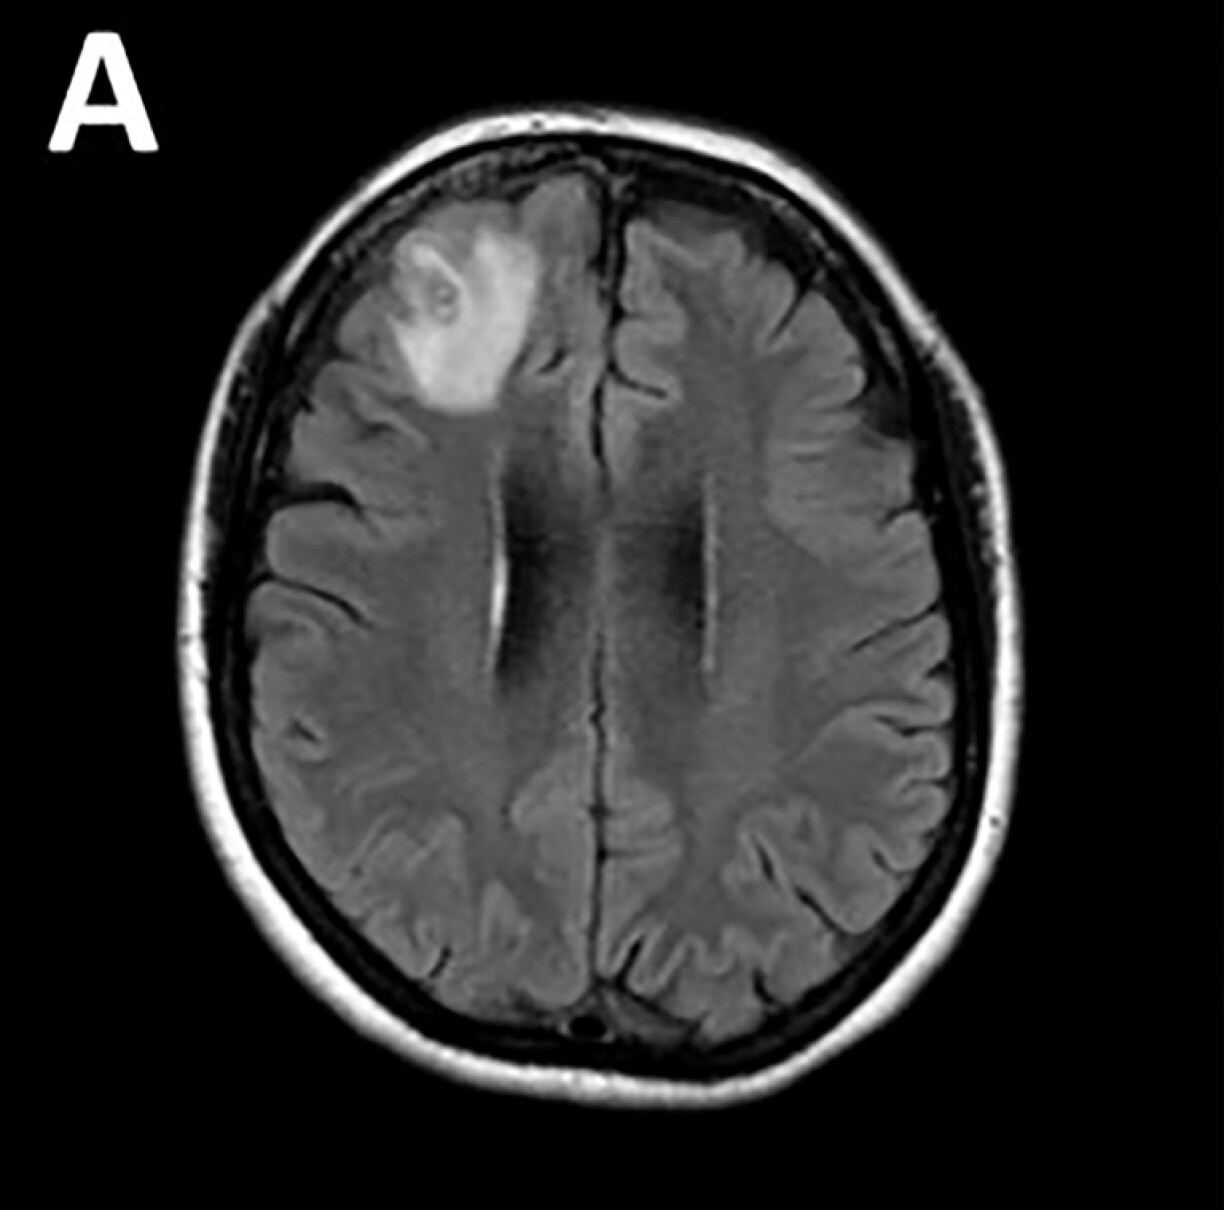

Les médecins ont découvert une “lésion atypique”, grâce à un examen IRM, dans la partie frontale du cerveau de l’Australienne, âgée de 64 ans, qui souffrait de pertes de mémoire.

Le ver, dont la “structure en forme de fil” est apparue sur les scanners cérébraux, a ensuite été identifié grâce à des tests ADN.